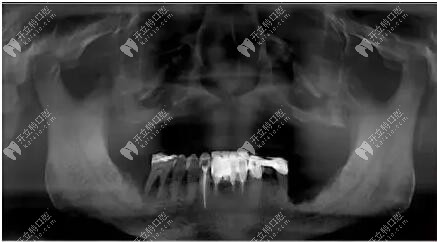

上圖看看這位大叔的具體情況

不得不說,這位大叔的上頜牙槽嵴還是屬于比較低平的,不過寬度不錯,檢查后上唇部塌陷,鼻唇溝加深,面下三分之一垂直距離變短,關(guān)節(jié)良好。

經(jīng)過拍片檢查上頜前牙區(qū)垂直骨較少,雙側(cè)上頜竇氣化明顯,患者選擇allon4和上頜結(jié)節(jié)種植,即刻修復。采用的是數(shù)字化導板種植,對于種植位置比較準確。